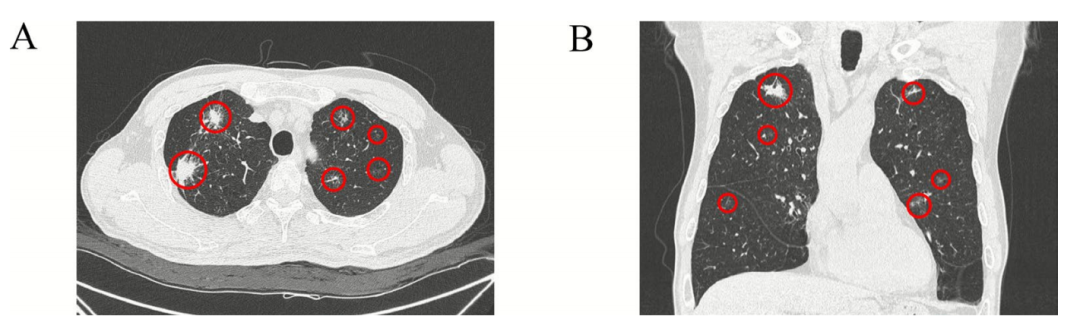

多发性肺结节的基线薄层CT

(A)同一水平的轴位视图显示多发性肺结节。(B)同一水平的矢状位视图显示多发性肺结节。